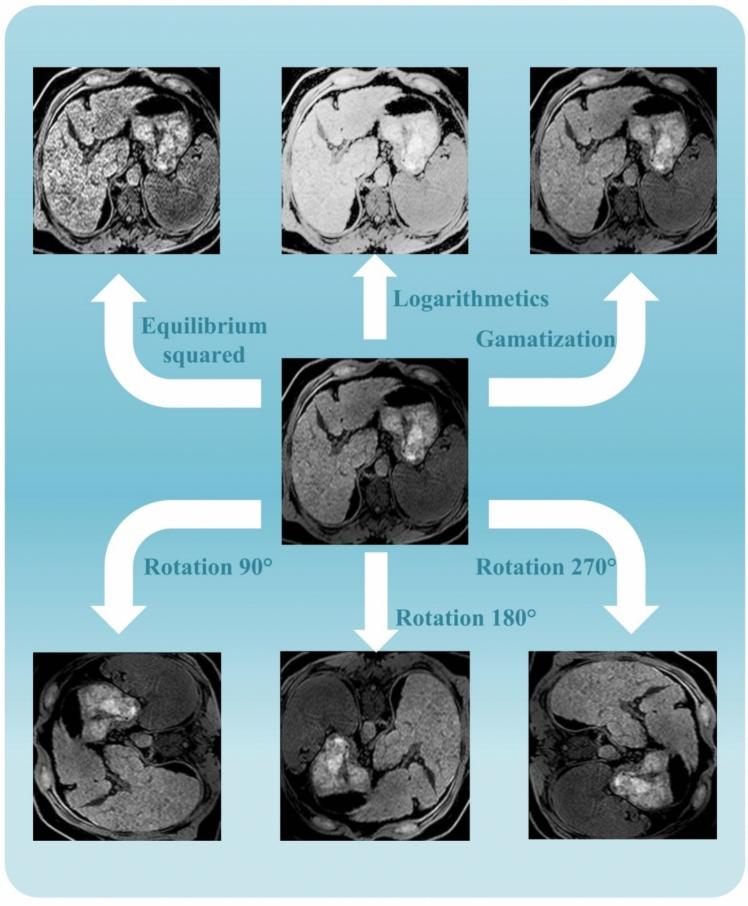

This study employed machine learning models to quantitatively analyze liver fat content from MRI images for the evaluation of liver fibrosis and disease severity in patients with metabolic dysfunction-associated fatty liver disease (MAFLD). A total of 26 confirmed MAFLD cases, along with MRI image sequences obtained from public repositories, were included to perform a comprehensive assessment. Radiomics features-such as contrast, correlation, homogeneity, energy, and entropy-were extracted and used to construct a random forest classification model with optimized hyperparameters. The model achieved outstanding performance, with an accuracy of 96.8%, sensitivity of 95.7%, specificity of 97.8%, and an F1-score of 96.8%, demonstrating its strong capability in accurately evaluating the degree of liver fibrosis and overall disease severity in MAFLD patients. The integration of machine learning with MRI-based analysis offers a promising approach to enhancing clinical decision-making and guiding treatment strategies, underscoring the potential of advanced technologies to improve diagnostic precision and disease management in MAFLD.

本研究采用机器学习模型对磁共振成像(MRI)图像中的肝脏脂肪含量进行定量分析,以评估代谢功能障碍相关脂肪性肝病(MAFLD)患者的肝纤维化和疾病严重程度。总共纳入了26例确诊的MAFLD病例以及从公共数据库获取的MRI图像序列,以进行全面评估。提取了诸如对比度、相关性、均匀性、能量和熵等放射组学特征,并用于构建具有优化超参数的随机森林分类模型。该模型表现出色,准确率为96.8%,灵敏度为95.7%,特异性为97.8%,F1分数为96.8%,证明其在准确评估MAFLD患者肝纤维化程度和整体疾病严重程度方面具有强大能力。机器学习与基于MRI的分析相结合,为加强临床决策和指导治疗策略提供了一种有前景的方法,凸显了先进技术在提高MAFLD诊断准确性和疾病管理方面的潜力。